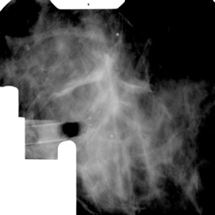

Die Lage des Befundes wird durch Mammografie-Aufnahmen aus unterschiedlichen Winkeln bestimmt. Dabei wird nur ein kleiner Anteil der Brust von 5 x 5cm Größe geröntgt. So kann mittels eines Computers die Lage des Befundes exakt bestimmt werden.